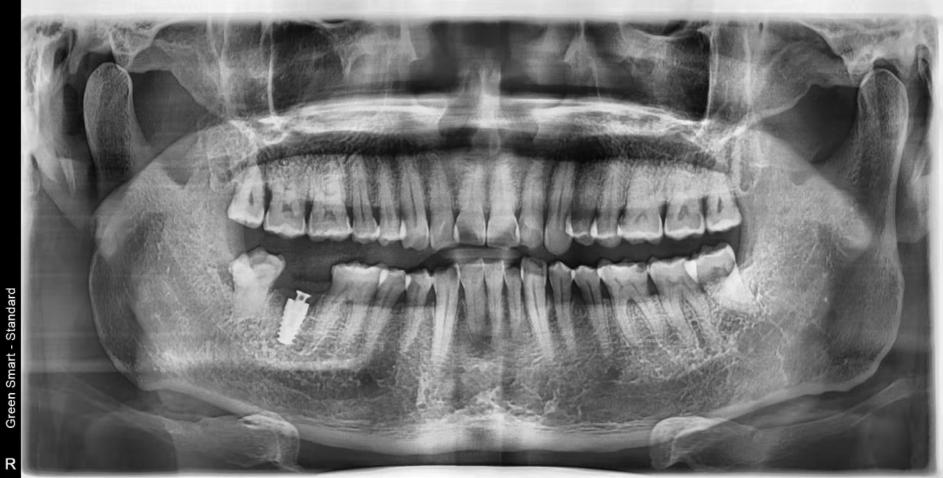

擅長多顆植牙及各類高難度複雜牙槽骨情況的植牙,案例二:

植牙前:

植牙後:(手術種植牙術後第一期照片)